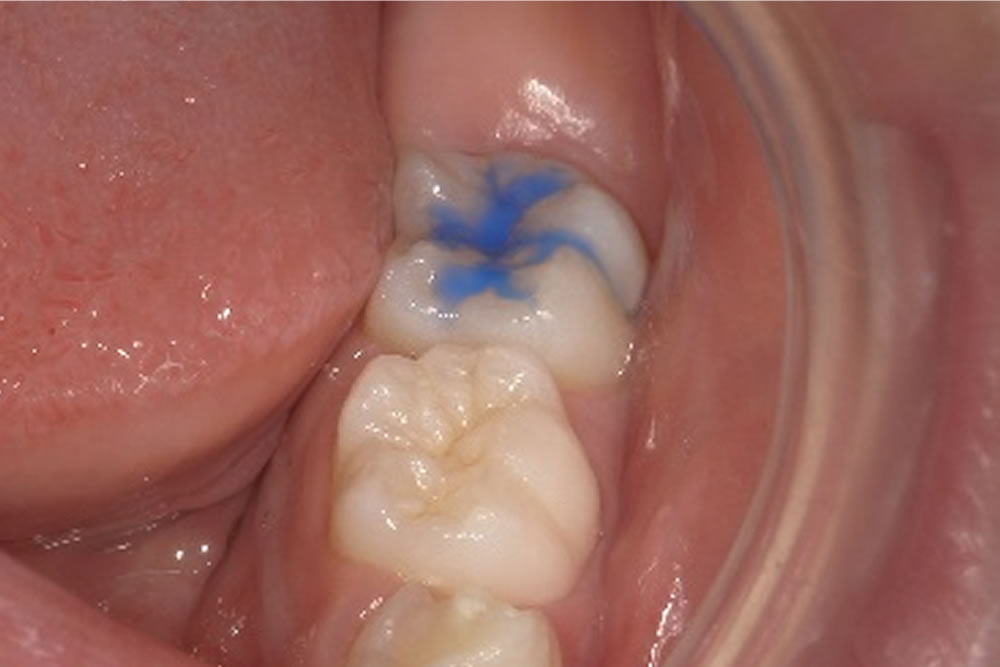

子供の虫歯予防対策「シーラント」を実施した症例

▼当院で実施したシーラントの症例をご紹介します。

処置前の口腔内

右下の6才臼歯(5~6才頃に生える初めての永久歯)に対し、シーラントを行います。シーラントとは、フッ素入りの乳白色の樹脂を歯の溝に埋める処置です。

生え変わったばかりの永久歯は抵抗力が低く、虫歯になりやすいという特徴があります。そのため、歯の溝を予め埋め、食べかすなどの蓄積防止とケアをしやすくすることで虫歯の予防リスクを軽減します。

シーラントの実施

| 年齢・性別 | 10代 女性 |

|---|---|

| 治療期間 | 1日 |

| 治療回数 | 1回 |

| 治療費 | 保険適用 |

| リスクなど | ・処置後すぐに食事をすると、外れてしまう場合がある。 ・日々のケアを怠ると虫歯になる可能性がある。 |